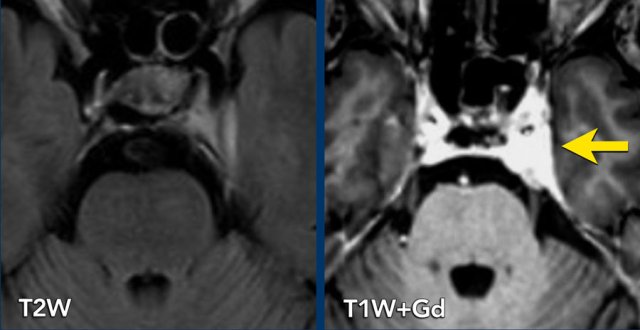

These images are of a 49-year old male with sensory problems in the left side of his face and pressure behind his left eye.

The axial T2W shows a lesion in Meckel’s cave and the cisternal segment of the trigeminal nerve. The component in Meckel’s cave is solid and shows homogeneous enhancement on post-contrast T1W imaging (arrow).

The component in the cerebellopontine cistern is almost completely cystic and shows only rim enhancement.

The lesion is a trigeminal schwannoma.

The growth of this lesion along the nerve, leading to a constriction at the entrance of Meckel’s cave, causes the classic ‘dumbbell shape’.